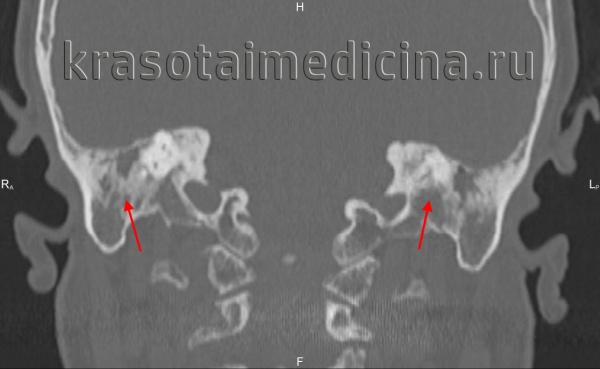

Компьютерная томография височных костей высокого разрешения (КТ) — это высокоинформативный объективный метод диагностики отосклероза. КТ позволяет точно визуализировать структуры височных костей, выявлять расположение, распространённость очагов и активность отосклероза. Также можно выявить очаги как пониженной, так и повышенной плотности.

Происходящие при отосклерозе изменения костной ткани капсулы лабиринта иногда определяются по результатам прицельной рентгенографии черепа. Однако более информативным исследованием является КТ черепа, позволяющая визуализировать очаги отосклероза.

КТ височных костей. С обеих сторон диффузное снижение пневматизации ячеек сосцевидного отростка и пирамиды височной кости за счет отосклероза